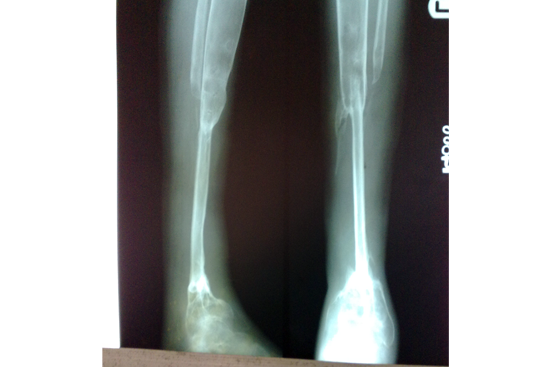

We have done Huntington technique by stage ilizarov procedure. Here is the diagrammatic representation of our method.